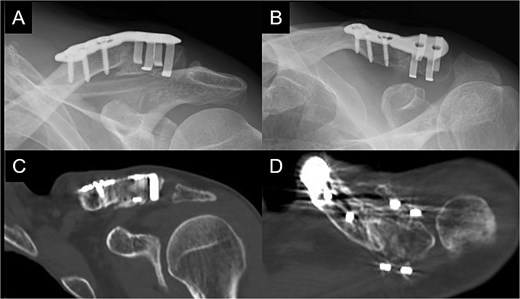

Postoperatively, the left arm of the patient was immobilized in a sling for 3 weeks. The pain gradually subsided, and the patient resumed heavy work without pain at 6 months postoperatively. At 1 year postoperatively, the patient had a constant score of 98. Bone union was confirmed (Fig. 4A–D).

Radiographs (A and B) and CT scans (C and D) captured at 1 year postoperatively show union of the bone.